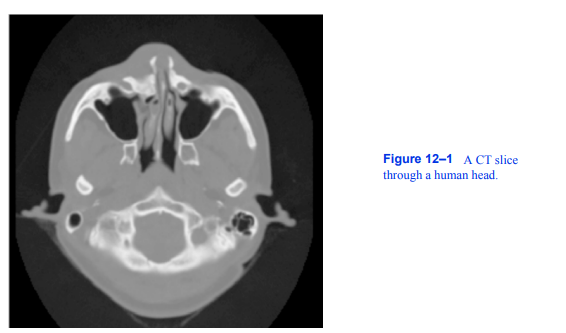

我们已经描述了一个广泛的可视化技术工具包的设计和实现。在本章中,我们将研究几个案例研究,以展示如何使用这些工具来深入了解重要的应用领域。这些领域包括医学成像、金融可视化、建模、计算流体动力学、有限元分析和算法可视化。对于每一种情况,我们简要描述了问题域,以及我们期望通过可视化获得哪些信息。然后我们设计一种方法来显示结果。很多时候,我们会使用特定于应用程序的工具来扩展可视化工具包的功能。最后,我们给

由vtkImageData类表示的图像数据集在拓扑和几何上是规则的,如图6-1所示。此数据类型是结构化的,这意味着数据点的位置仅使用几个参数(origin、spacing和dimensions)隐式定义。医学和科学扫描设备,如CT、MRI、超声扫描仪和共聚焦显微镜经常产生这种类型的数据。从概念上讲,vtkImageData数据集由体素(vtkVoxel)或像素(vtkPixel)单元组成。然而,这